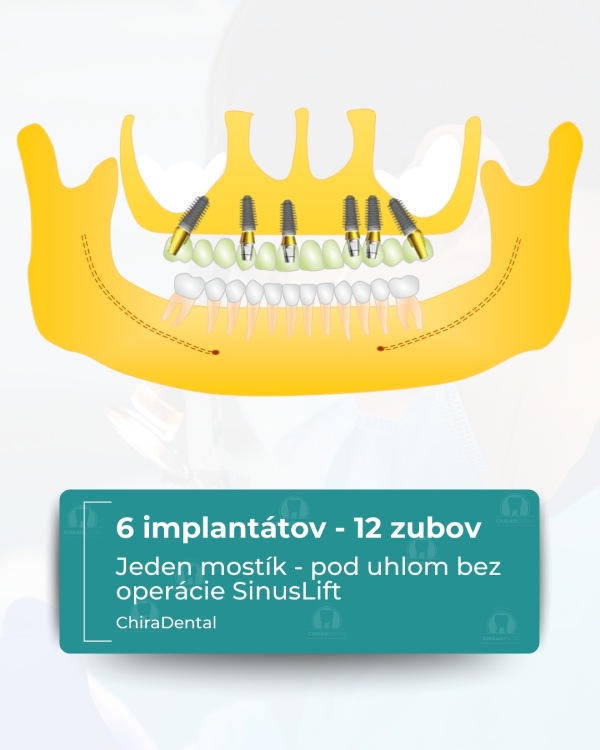

Moderné technológie umožňujú rýchlo, spoľahlivo a esteticky obnoviť celú čeľusť, a to aj v zložitých prípadoch. Ponúkame niekoľko kompletných rehabilitačných systémov založených na počte implantátov a úrovni fixácie budúcej štruktúry. Možnosť 1 - All-on-4 (Základné riešenie) Táto metóda je vhodná pre pacientov so zníženým objemom kosti alebo pre tých, ktorí chcú nové zuby čo najrýchlejšie. Čo robíme: Inštalujeme 4 implantáty do hornej alebo dolnej čeľuste; V prípade potreby vykonáme augmentáciu kosti a plastiku ďasien počas tej istej návštevy; Nasledujúci deň odoberieme odtlačky pre dočasnú štruktúru; Po 3-5 pracovných dňoch pacient dostane dočasné kovovo-akrylátové zuby na dlhodobé nosenie. Výsledok: približne 10 nových zubov, ktoré umožňujú pohodlné žuvanie a úsmev. Po 3-6 mesiacoch vykonávame trvalé rekonštrukcie s použitím kovovo-keramiky alebo zirkónu. ⭐ Možnosť 2 — All-on-6 (štandardné riešenie) Optimálna možnosť pre pacientov, ktorí vyžadujú väčšiu stabilitu a väčšiu žuvaciu záťaž. Čo robíme: Inštalácia 6 implantátov so súčasnou augmentáciou kosti a ďasien; Odtlačky sa robia nasledujúci deň;Dočasné kovovo-akrylátové korunky sa inštalujú po 3-5 dňoch.

Výsledok: kompletný oblúk 14 zubov. Definitívna rekonštrukcia (kovovo-keramika alebo zirkón) sa vykonáva po 3-6 mesiacoch.